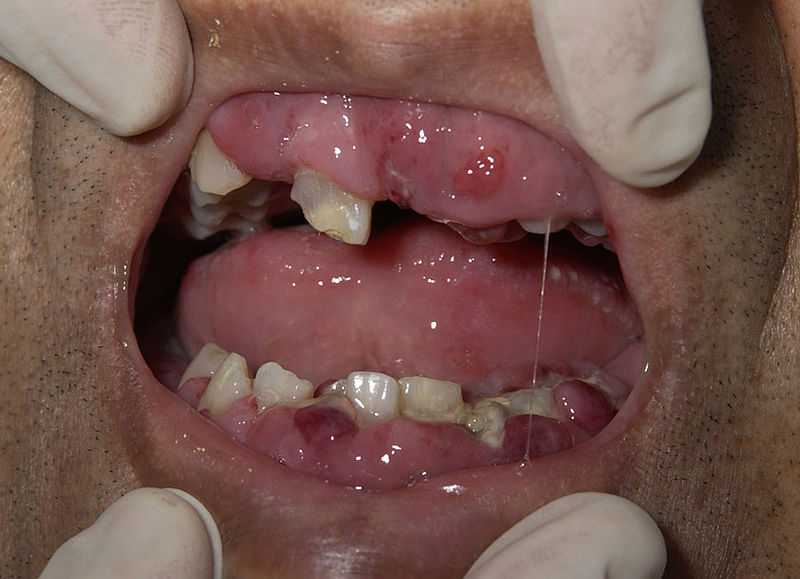

Acute Monocytic Leukemia

Acute monocytic leukemia is a subtype of acute myeloid leukemia (AML).

Acute monocytic leukemia is characterized by the growth of monoblasts and typically lacks MPO.

These blasts characteristically infiltrate gums.